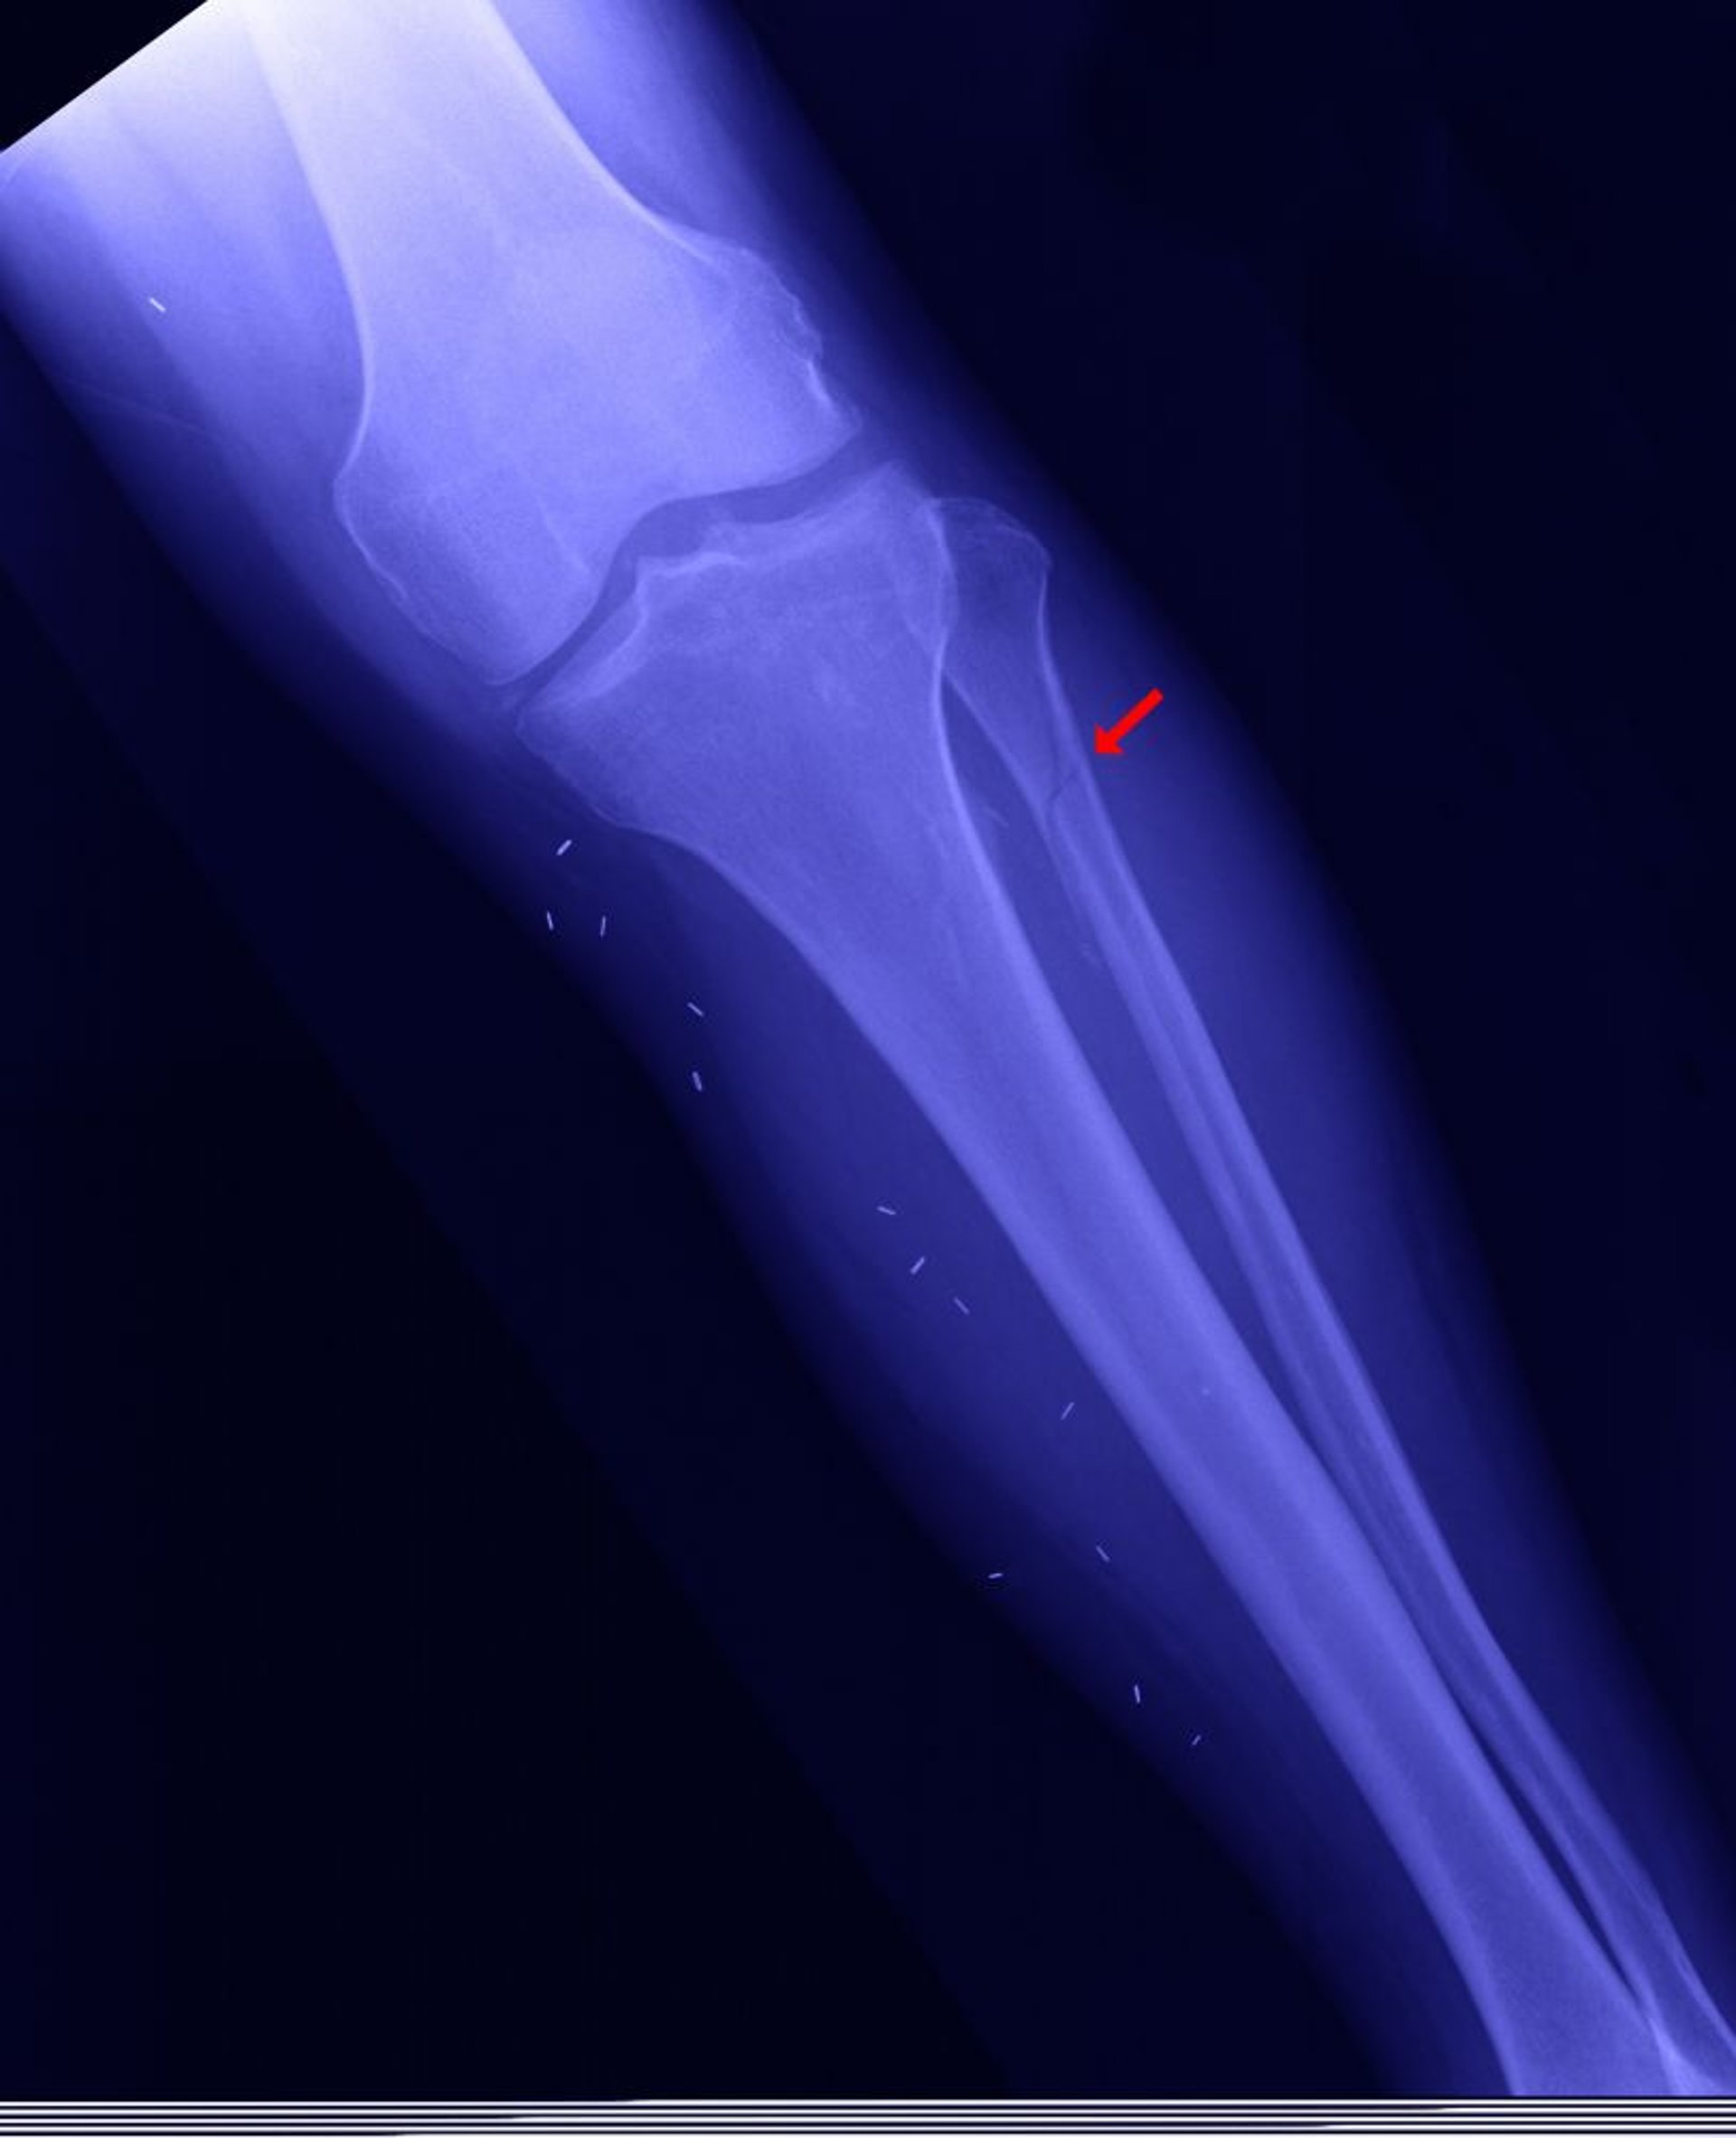

Перелом проксимального отдела малоберцовой кости

Проксимальный отдел малоберцовой кости может быть сломан (так называемый перелом Мезоннева показан здесь), когда медиальная лодыжка сломанная, межберцовый паз (место соединения между голенью и таранной костью) открыт, а дистальный отдел малоберцовой кости не сломан.

EDWARD KINSMAN/SCIENCE PHOTO LIBRARY